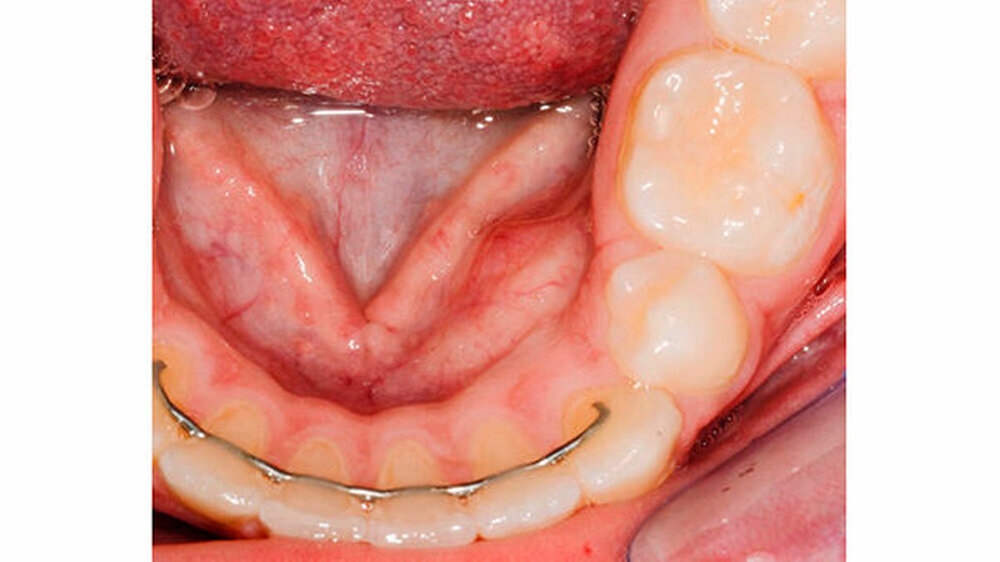

Der extraorale Befund zeigte eine normale Sensibilität der Unterlippe. Intraoral am Alveolarfortsatz des linken Unterkiefers regio 32-34 lingual konnte eine circa 2×2,5 cm große, schmerzreie knöcherne Vorwölbung palpiert werden (Abbildung 1). Die Zähne 31-36 reagierten normal auf den Test mit CO2-Schnee.